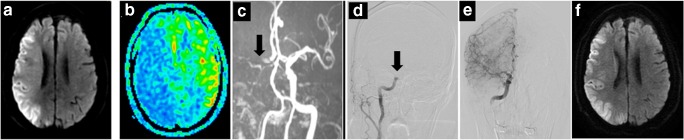

Fig. 2.

A 85-year-old man (NO. 3 in Supplementary Tables 1 and 2) with a DWI-ASPECTS of 2 and an ASL-DWI mismatch ratio of 1.95, received bridging therapy and obtained successful reperfusion at 155 min from onset. This patient achieved a favorable outcome as 3 months (mRS = 2). a Infarction lesion presented on DWI (shown as high signal). b Hypoperfusion area shown on ASL-CBF map (blue). c Right ICA occlusion shown on MRA (black arrow). d DSA showing occlusion site of right ICA (black arrow) before EVT. e DSA showing reperfusion of occlusion vessel after EVT. f DWI image at 24 h after EVT